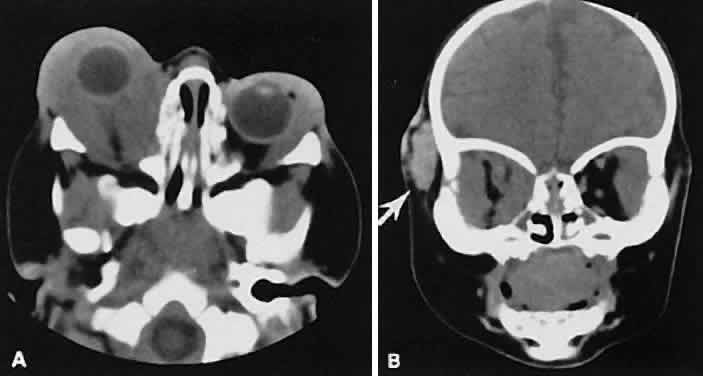

Dermoid cysts are located most frequently in the superior temporal quadrant of the orbit. They may be located anywhere within the orbital confines. Lesions in the lacrimal fossa or along the posterior lateral wall may communicate intracranially or into the temporalis fossa. Radiographically, the cysts are well-delineated and have lucent interiors with CT attenuation densities in the fat range (Fig. 19). Calcification along the rim of the cyst may be present. The bony changes have irregular, notched borders rather than the moth-eaten appearance associated with malignancy. The range of CT appearances can be quite wide.67

Fig. 19. Axial (A) and coronal (B) scans of a dermoid cyst. Note the low attenuation (lower than retrobulbar fat) within the well-demarcated cyst located in the right lacrimal gland fossa.